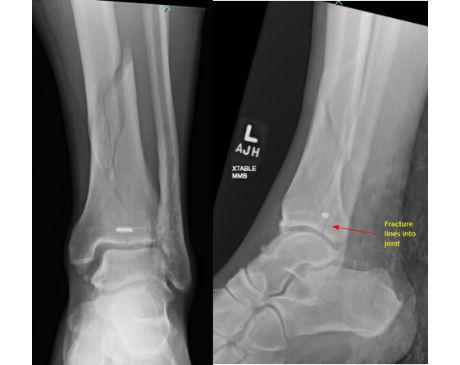

I was hit by car, had a compound fracture with a bone sticking out of my left foot. Broken tibia and fibia?. Screwed plate and bones back together. I am healing fine, next visit 3/26 to remove stiches. I seem to have total function of foot. Still have 2 more weeks of not using leg, but very hopeful.